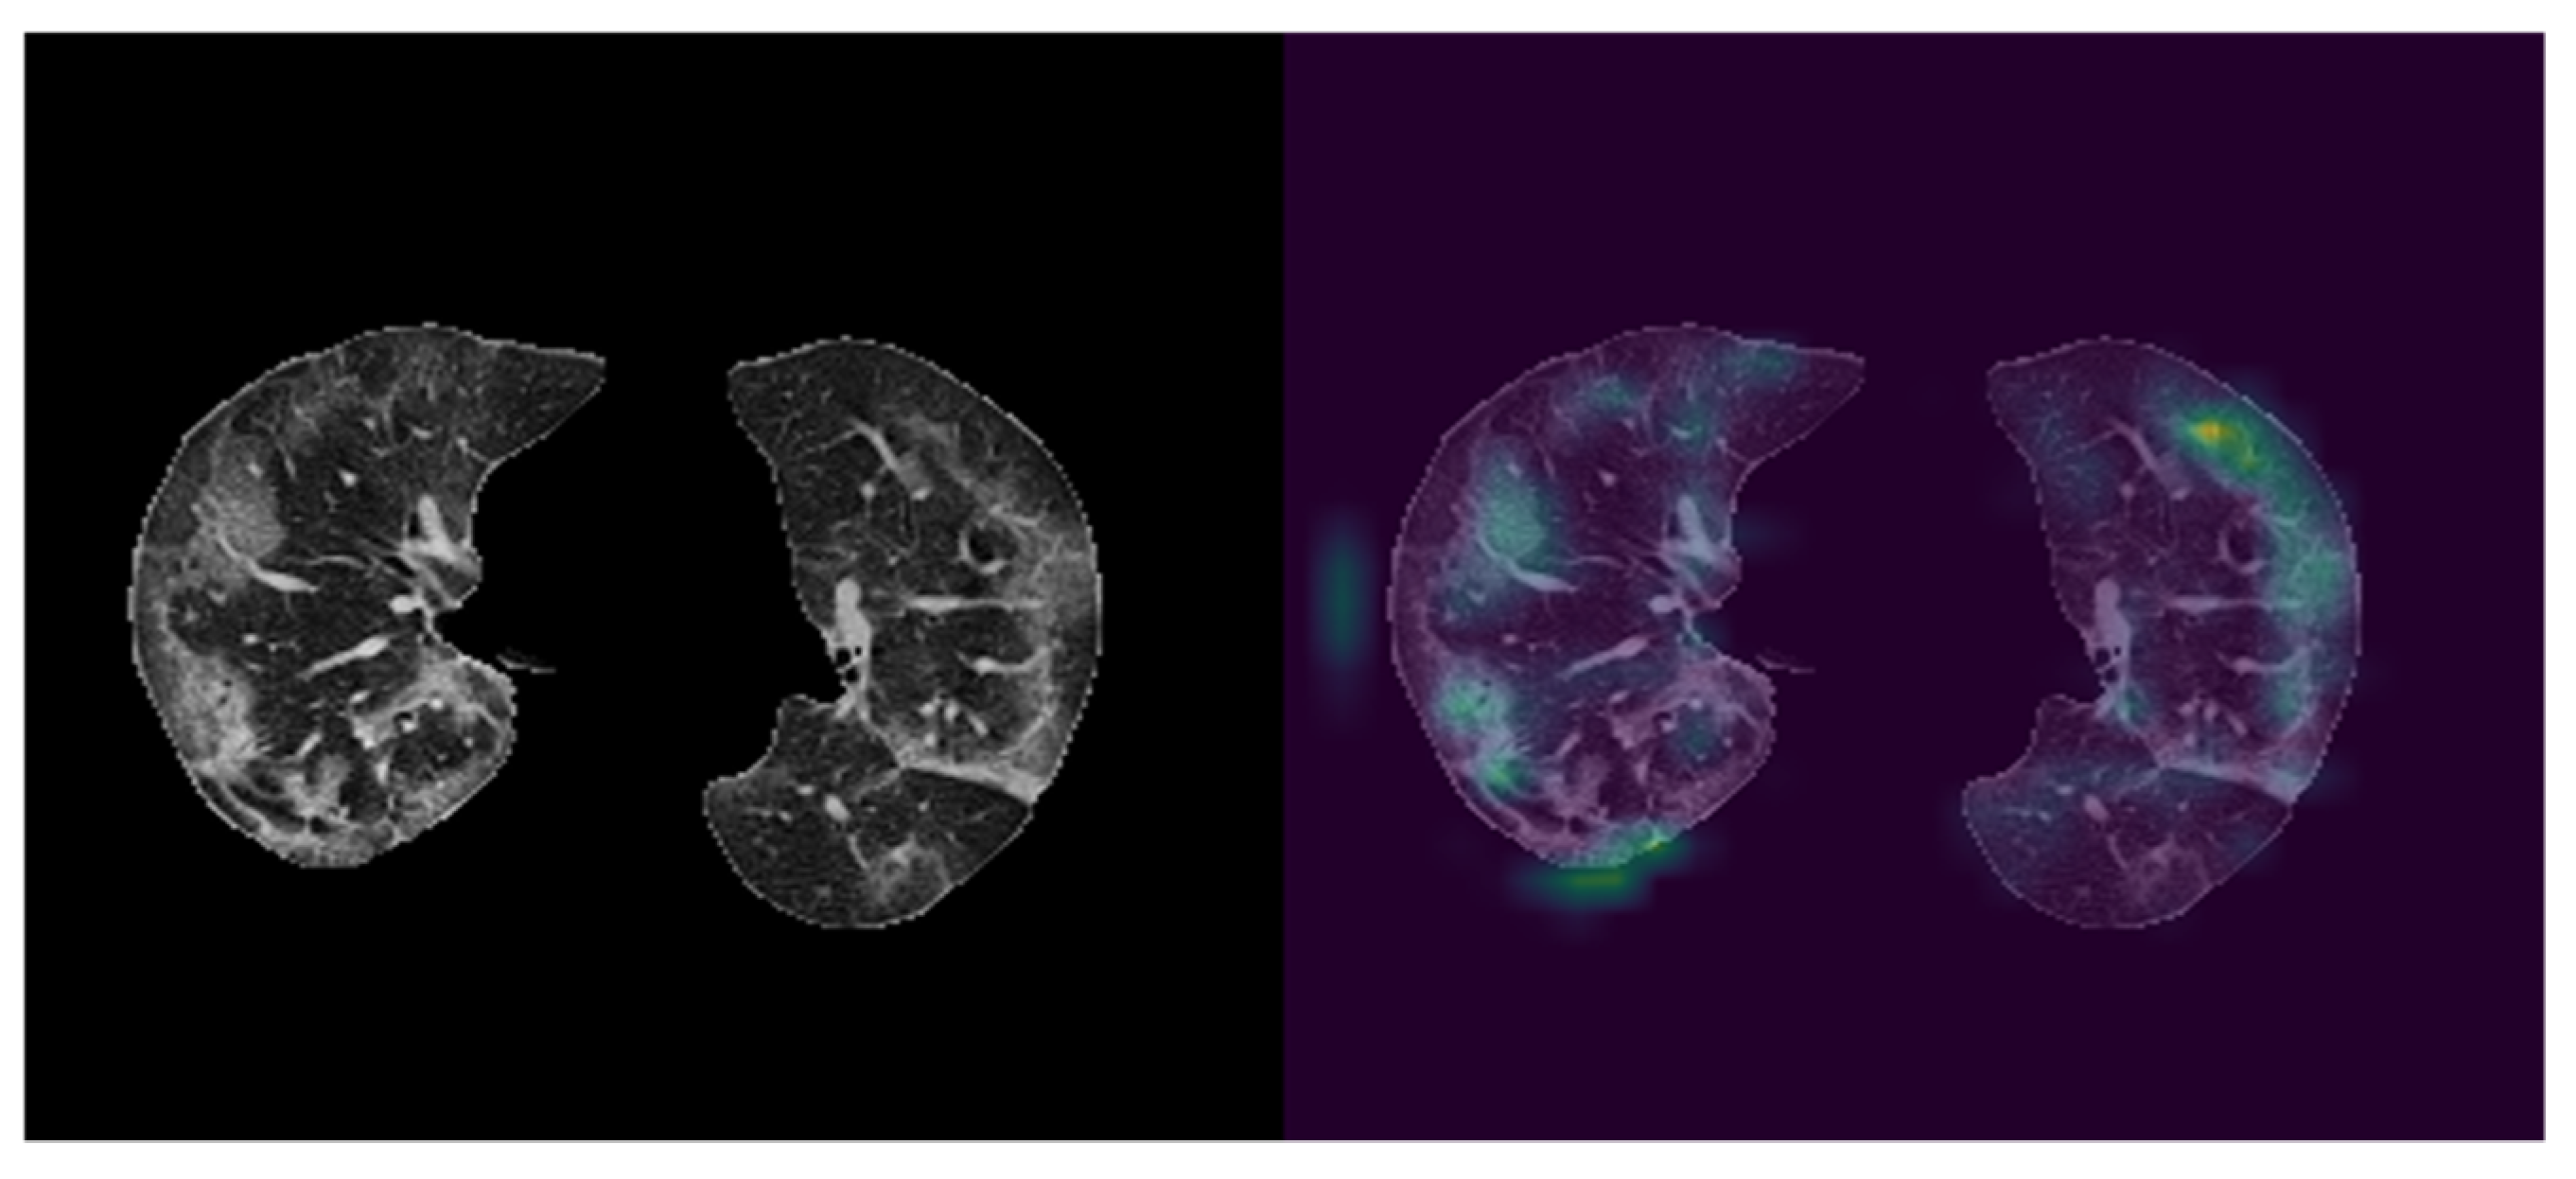

CNN blocks of the proposed network were utilized to obtain feature maps of ground glass opacities (GGO). To illustrate the effectiveness of the approach used in this study, the last class activation map (CAM) was visualized with the help of Grad-CAM (Figure 5). As it can be seen from Figure 5, features were primarily extracted from ground glass opacities.

Figure 5. Visualization of CNN outputs. left: Cropped CT image, right: visualized feature map of CNN output. The right image shows CNN blocks are capable of capturing Ground Glass Opacities in CT images.